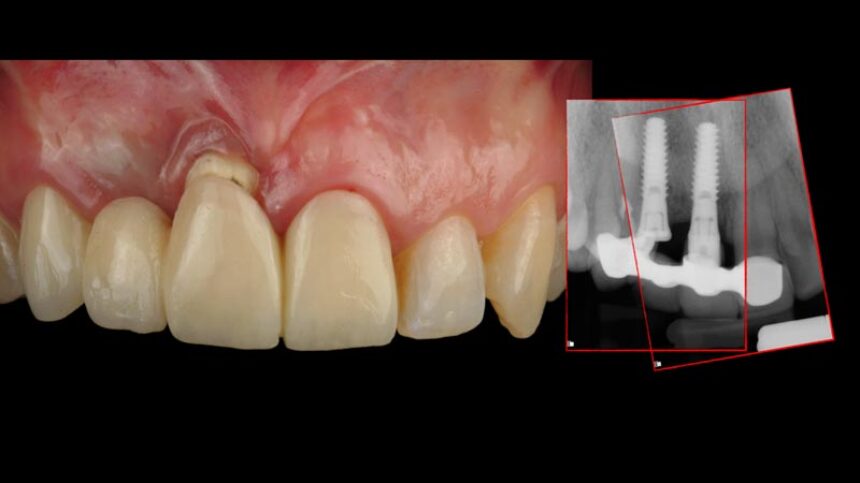

Διάγνωση, πρόληψη και αντιμετώπιση της περι-εμφυτευματίτιδας

Διαχείριση των αποτυχιών των εμφυτευμάτων στην αισθητική περιοχή, οι εναλλακτικές.